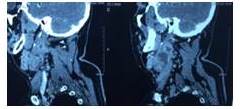

Acude a médico en otro centro asistencial quien describe que al examen físico evidencia lesión de aproximadamente 4 cm de diámetro, ubicada en el triángulo anterior de cuello, anterior al músculo esternocleidomastoideo en su tercio superior, procediendo a realizar estudio tomográfico (Figura 1,2 y 3) y exéresis del mismo.

Es evaluado por nuestro centro, donde se realiza anamnesis y posteriormente el examen físico, exhaustivo incluyendo nasofibrolaringoscopia no evidenciando tejido amigdalino palatino ni lesiones en el tracto aéreo digestivo superior. Al tacto intraoral, de orofaringe incluyendo base de lengua, no se palpaban lesiones. Se observa estudio de TAC de cuello con contraste intravenoso, con cortes axiales, coronales y sagitales, previa a intervención, mostrando una lesión mixta, de 4 cm de diámetro, por delante del esternocleidomastoideo, nivel II, con algunas adenopatías en el mismo nivel y III entre 1 cm y 1,5 cm, no confluentes. No se observan tumoraciones en el resto del estudio. En la tomografía realizada en nuestro centro, no se observan lesiones, a tres meses de la extirpación de la lesión (Figura 4).